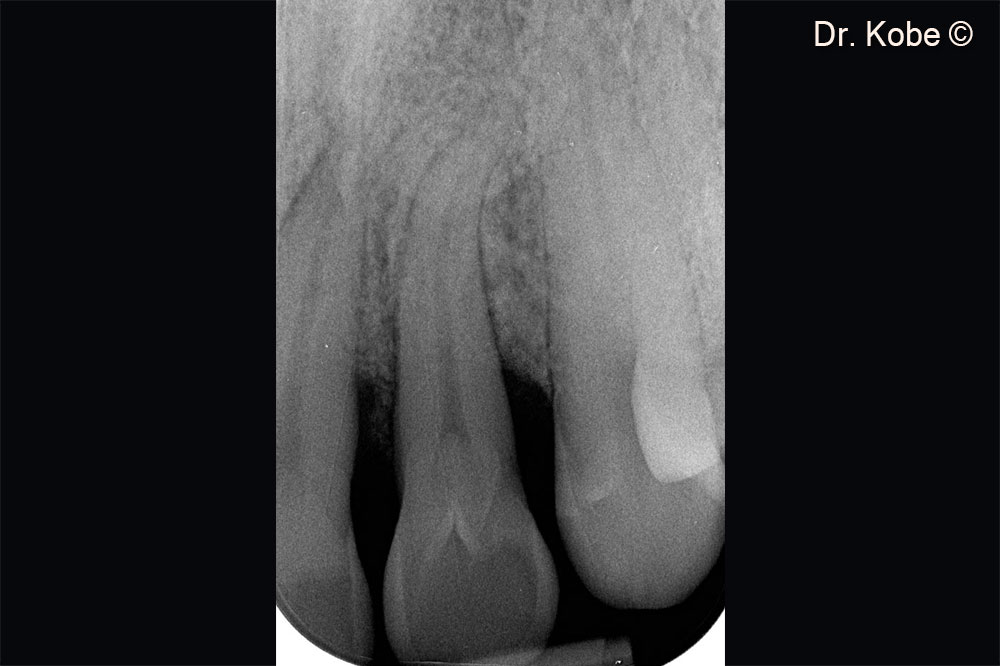

Vertical bone defect on the radiograph